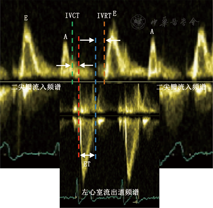

是1995年由日本学者Tei等[2]提出的一个评价心脏收缩与舒张整体功能的参数。可由脉冲多普勒或者组织多普勒测量获取等容收缩期(IVCT,二尖瓣A峰结束至左心室流出道频谱起始时间)、等容舒张期(IVRT,左心室流出道频谱结束至E峰起始时间)和射血时间(ET,左心室流出道频谱持续时间)。MPI(Tei指数)= (IVCT + IVRT)/ET,当左心室收缩功能减退时,IVCT和IVRT延长以及ET缩短,因此MPI测量值增大。因其可以准确估测心脏整体功能,具有简便、敏感性高、重复性好的优点。MPI>0.47提示左心室收缩功能减低。见图3。

注:MPI心肌做功/活动指数;E二尖瓣E峰;A二尖瓣A峰;二尖瓣流入频谱E峰起始至A峰结束;左心室流出道频谱单峰频谱;IVCT等容收缩期(A峰结束至左心室流出道频谱起始时间);IVRT等容舒张期(左心室流出道频谱结束至E峰起始时间); ET射血时间(左心室流出道频谱持续时间)